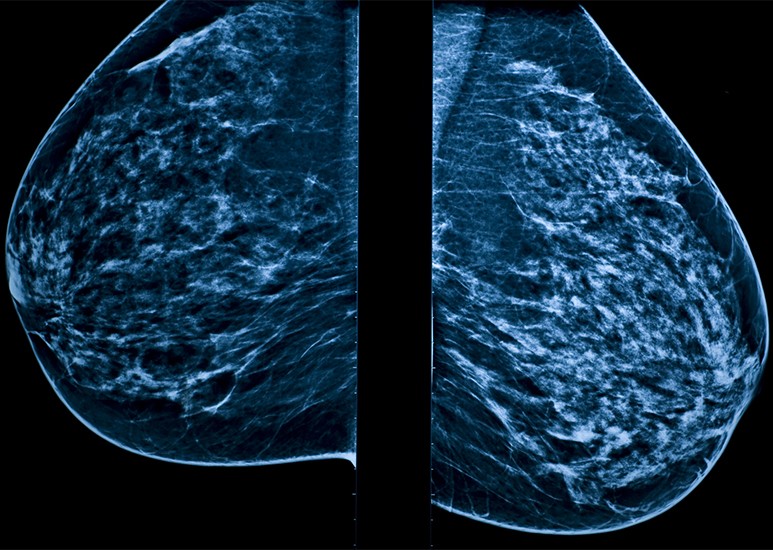

3D mammogram diagnostic image

3D mammography is an advanced imaging technique to help discover breast cancer. 3D mammograms provide a clearer view of breast tissues and a better chance of spotting abnormalities than traditional 2D mammograms. With this enhanced detection rate, 3D mammography is an essential tool in safeguarding women’s health.

A detailed, 3D model of your breast is created from the images taken during compression and then analyzed by a radiologist, a doctor who specializes in imaging. This model allows the doctor to more accurately review and assess any potential abnormalities, especially in denser breast tissue. With this improved precision, doctors feel more confident in their evaluation and are less likely to call you back for a second look.

The images also allow the doctor to determine your breast tissue density, which can only be seen on a mammogram and cannot be determined from a manual exam. There are four main types of breast density: fatty, scattered, heterogeneously dense and extremely dense. Dr. Zusan wants women to understand that, “Knowing your breast density is important because dense tissue can make it harder for the doctor to see abnormalities on your mammogram and can contribute to your lifetime risk of breast cancer.” Women with dense breast tissue may need additional imaging so that the radiologist can get a clearer picture of any changes in breast health.